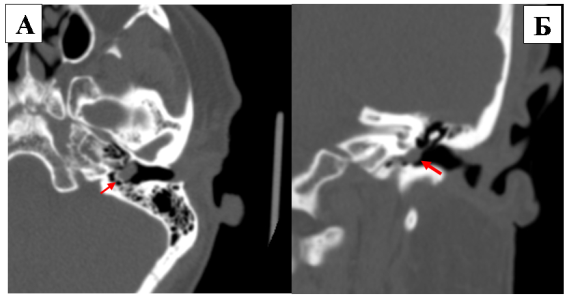

Рис. 1

На рисунке 1А представлена иллюстрация аксиального среза левой височной кости на которой изображена классическая аберрантная внутренняя сонная артерия (АбВСА), берущая свое начало вдоль задних отделов мыса барабанной полости, идущая вдоль медиальной стенки среднего уха и сливающаяся с горизонтальным сегментом каменистого отдела внутренней сонной артерии (ВСА). В точке соединения горизонтального сегмента каменистого отдела внутренней сонной артерии (ВСА) часто может отмечаться стеноз артерии.

На рисунке 1Б представлена КТ-ангиография, аксиальный срез через среднее ухо: аберрантная внутренняя сонная артерия, идущая петлеобразно вокруг низкого мыса барабанной полости.

Рис. 3

На рисунке 3А представлена КТ-ангиография. В аксиальной проекции височной кости визуализируется АБВСА меньшего размера, входящая в полость среднего уха по расширенному нижнему барабанному канальцу, проходящая поперек мыса улитки, и сообщающаяся с горизонтальным каменистым сегментом ВСА.

На рисунке 3Б КТ-ангиография в корональной проекции. Левая височная кость на уровне овального окна визуализируется АБВСА в виде «объемного образования» на мысе улитки, напоминающего гломусную тимпаническую параганглиому.